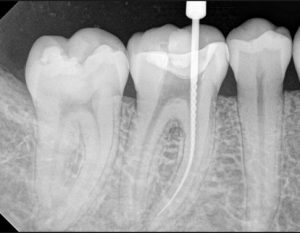

La terapia endodóntica consiste en la extirpación total de lapulpa dental (nervio-arteria-vena) Se aplica en piezas dentales fracturadas, con caries profundas o lesionadas en su tejido pulpar.

Y el estudio de la Patología Periapical Esta es irreversible y la única opción terapéutica es la extirpación total de la pulpa dental, y la obturación tridimensional del conducto dentario.